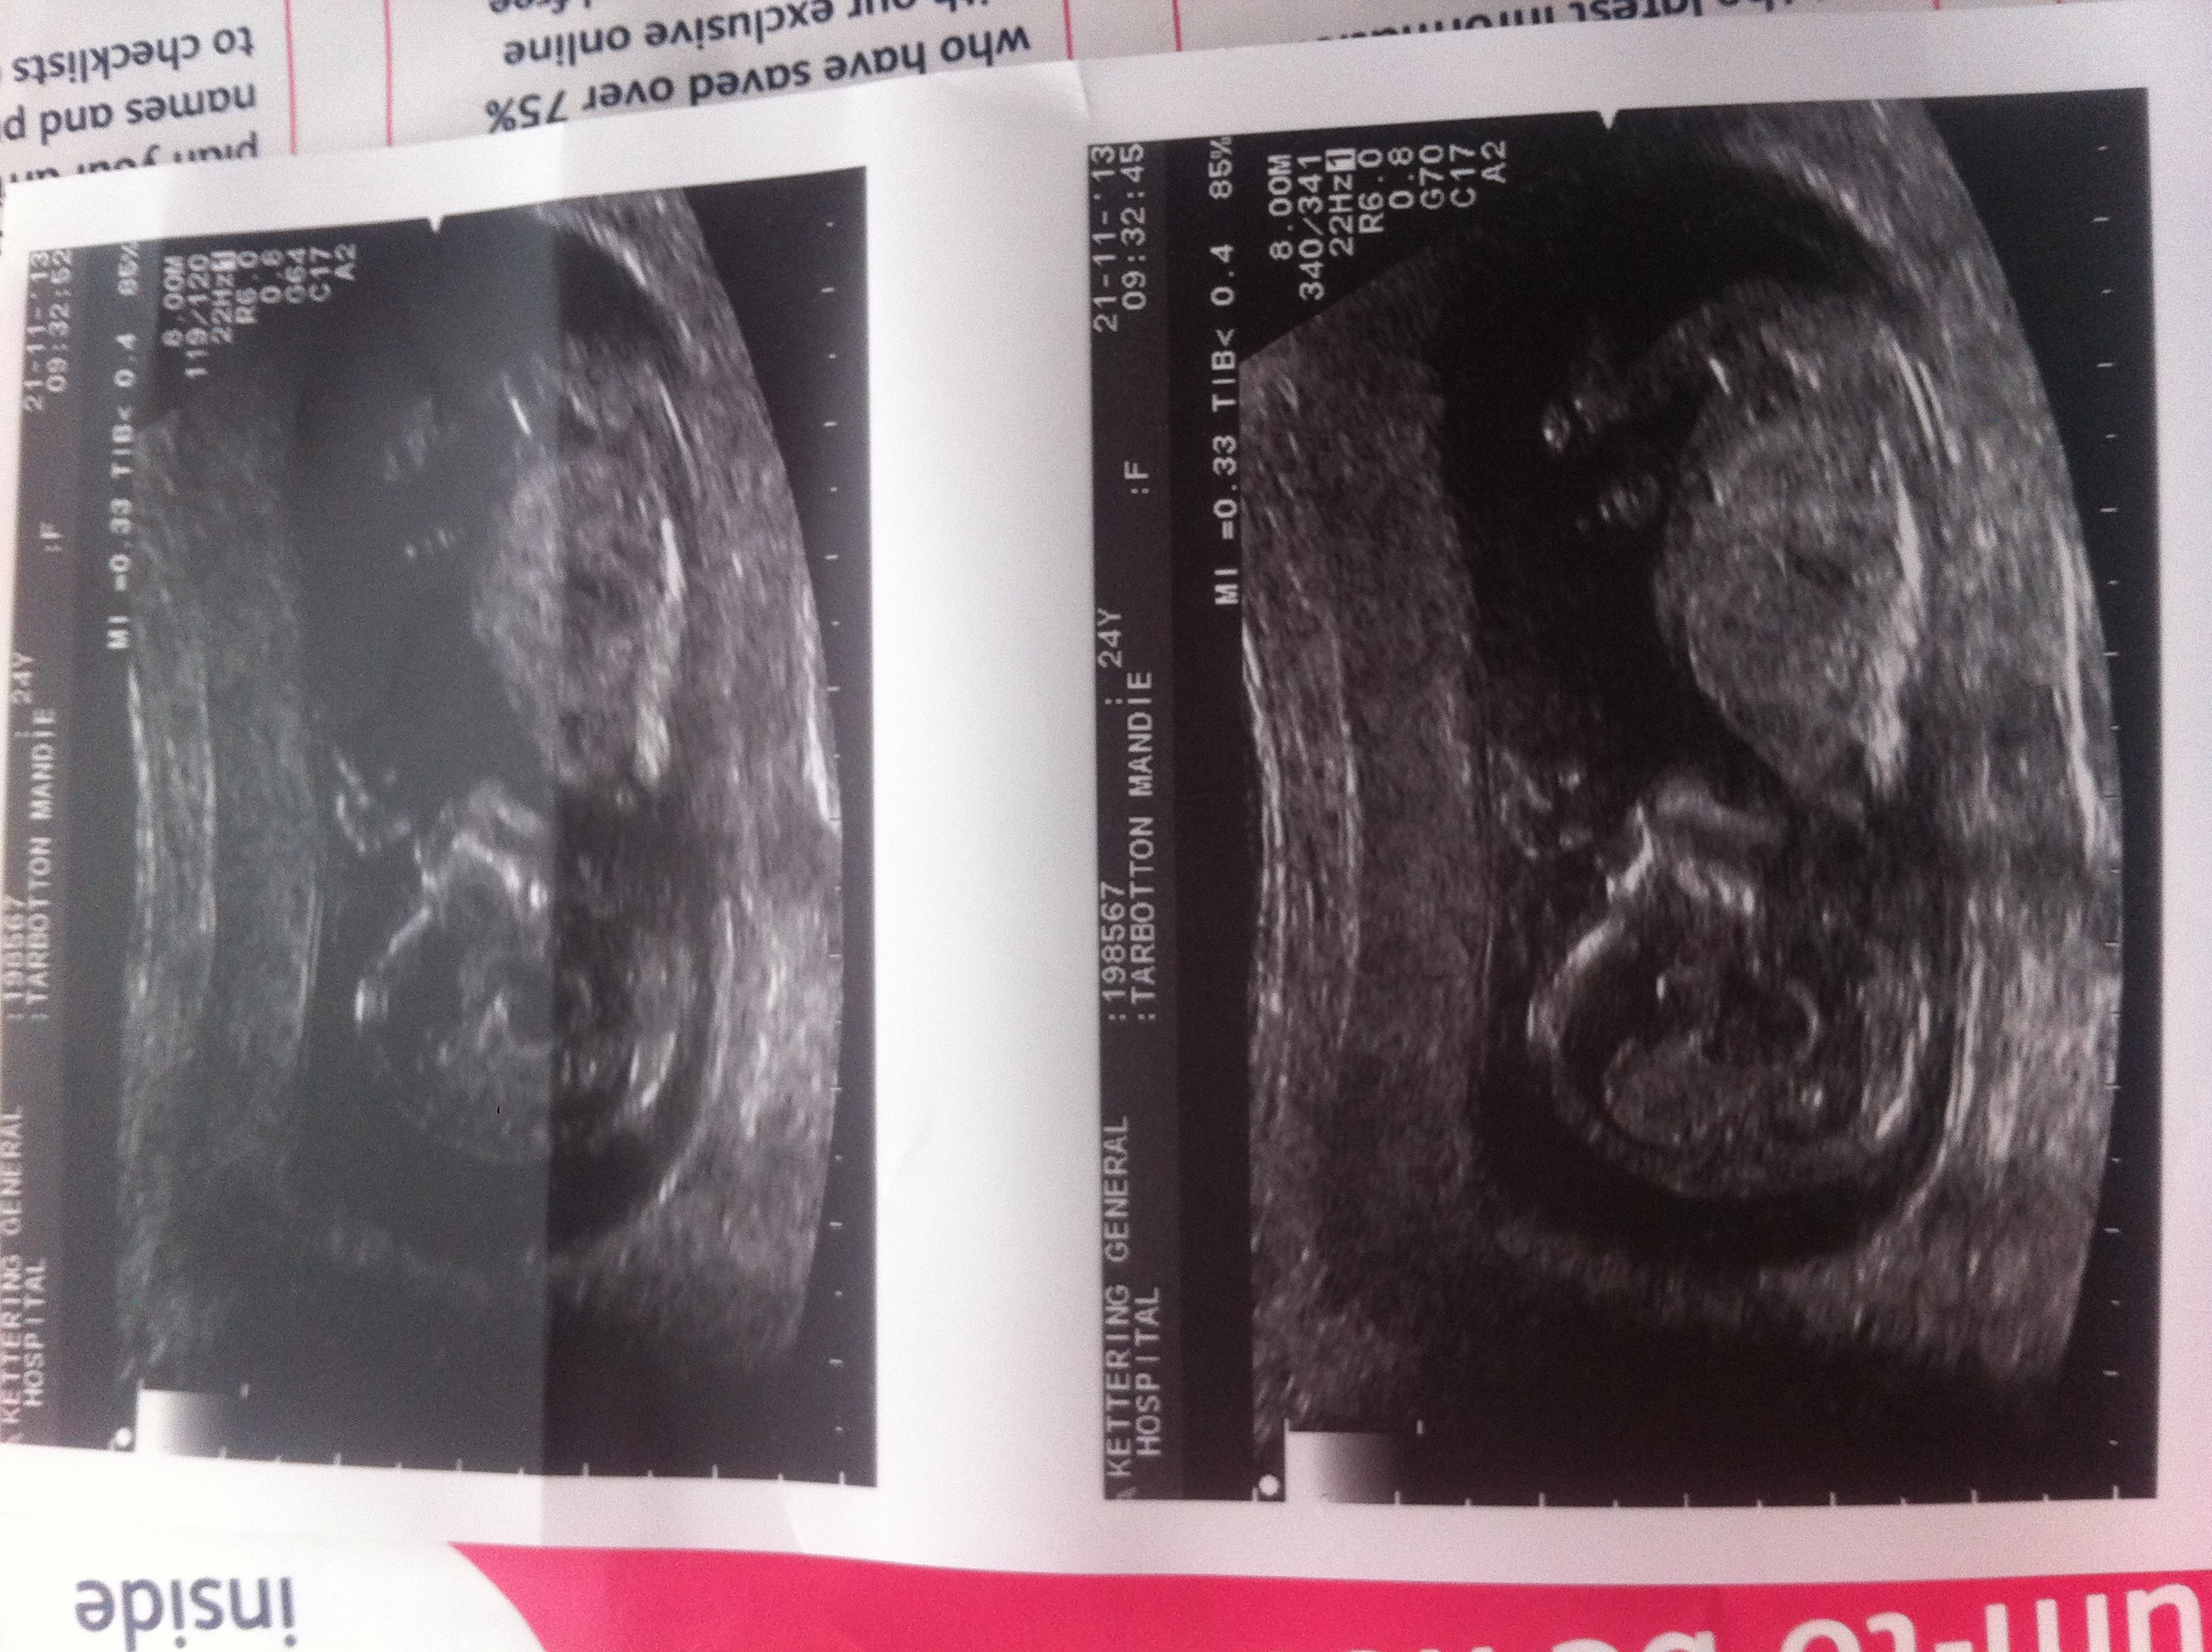

12w6d ultrasound. Any guesses as to what gender my baby is? Sonography e said baby looks very neutral and is keeping its cards close to chest lol. Thabkyou

I think I can see a nub but I'm not 100% sure, if it is a nub indeed you're looking at a boy!!! Congratulations!! Would you like to have a look at mine??

Boy :D

I think boy but not super clear pics, good luck!!

If thats a nub im seeing then i say boy!